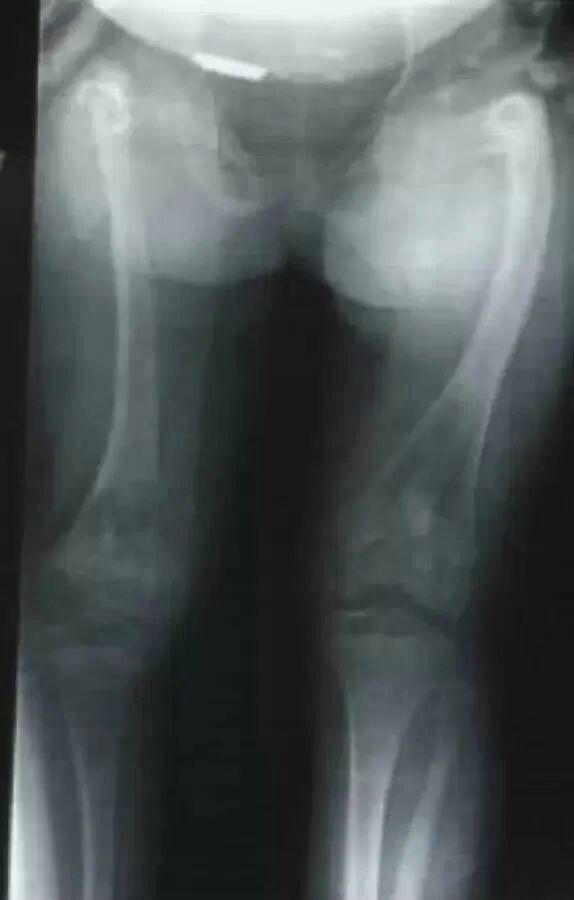

入院检查:患者男性,16岁,因“外伤致右大腿肿痛伴活动受限2天”;体查:平时坐轮椅生活,身高: 132cm,体重: 43kg,蓝巩膜,双下肢弯曲畸形,X形腿右下肢石膏固定,右大腿稍肿胀,压痛,可及骨擦感。辅查:本院X线及CT(见图一):右股骨干下段骨折,骨质疏松,双下肢弯曲畸形,胸片及ECG无明显异常;其他:既往史无特殊,父母及1兄弟均无遗传病史。

治疗方案:1.右侧股骨干骨折伴畸形多段截骨矫形髓内钉固定术2.左侧股骨干畸形多段截骨矫形髓内钉固定术。

OI标志性特征是骨质脆弱反复骨折, 典型骨骼X线表现(见图二);成骨不全症的临床表现不仅限于骨骼,还常常累及其他结缔组织如眼、耳、皮肤、牙齿等(见图三)。根据临床表型, 澳洲悉尼大学的Sillence教授将OI 分成至Ⅰ-Ⅳ型[7]: Ⅰ型病情最轻, 最常见; Ⅱ最重, 通常围产期致死; Ⅲ型是存活者中最严重的, 常常身材矮小, 呈进行性骨骼畸形; Ⅳ型严重度介于Ⅰ型与Ⅲ型之间。近期发现的Ⅴ型OI 具有肥厚性骨痂、桡骨头脱位、前臂骨间膜钙化、桡骨干骺端下密集骺线等独特临床表现(见图四)。